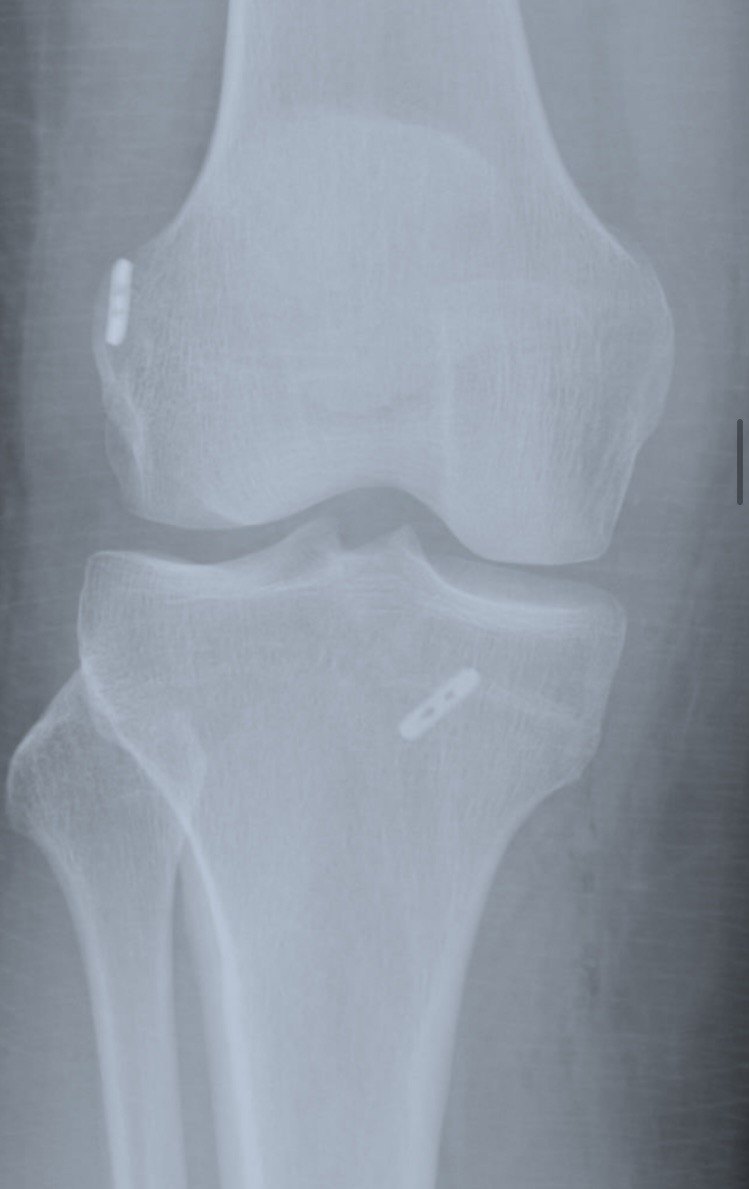

«Дивно», — подумала і таки записалася до приватного ортопеда. Знаного. Не будь-кого. Пришкандибала в кабінет через тиждень після травми. Лікар оглянув, провів тести: «200 %, що у вас розірвана передня хрестоподібна зв’язка. Є два варіанти: нічого не робити (жити так) або операція».

Операція зветься артроскопія. Суть втручання в тому, що з вашої ж іншої жилки формують нову хрестоподібну зв’язку, дірявлять суглоб і кріплять металом нову зв’язку. Далі — місяці реабілітації, а тоді можна хоч у гори пішки.

Оглянув, підтвердив порваність зв’язки, показав, де ще інші пошкодження в коліні сталися — дві тріщини і порваний меніск.

Як писала вище, з останнім хірургом у нас стався метч. Він навіть дозволив подивитися на власну операцію. Адже для неї медикаментозний сон не обов’язковий, достатньо спінальної анестезії. Як цікаво! Це ж можна побачити, як свердлять мій суглоб і чіпляють туди два крихітні титанові ґудзики!